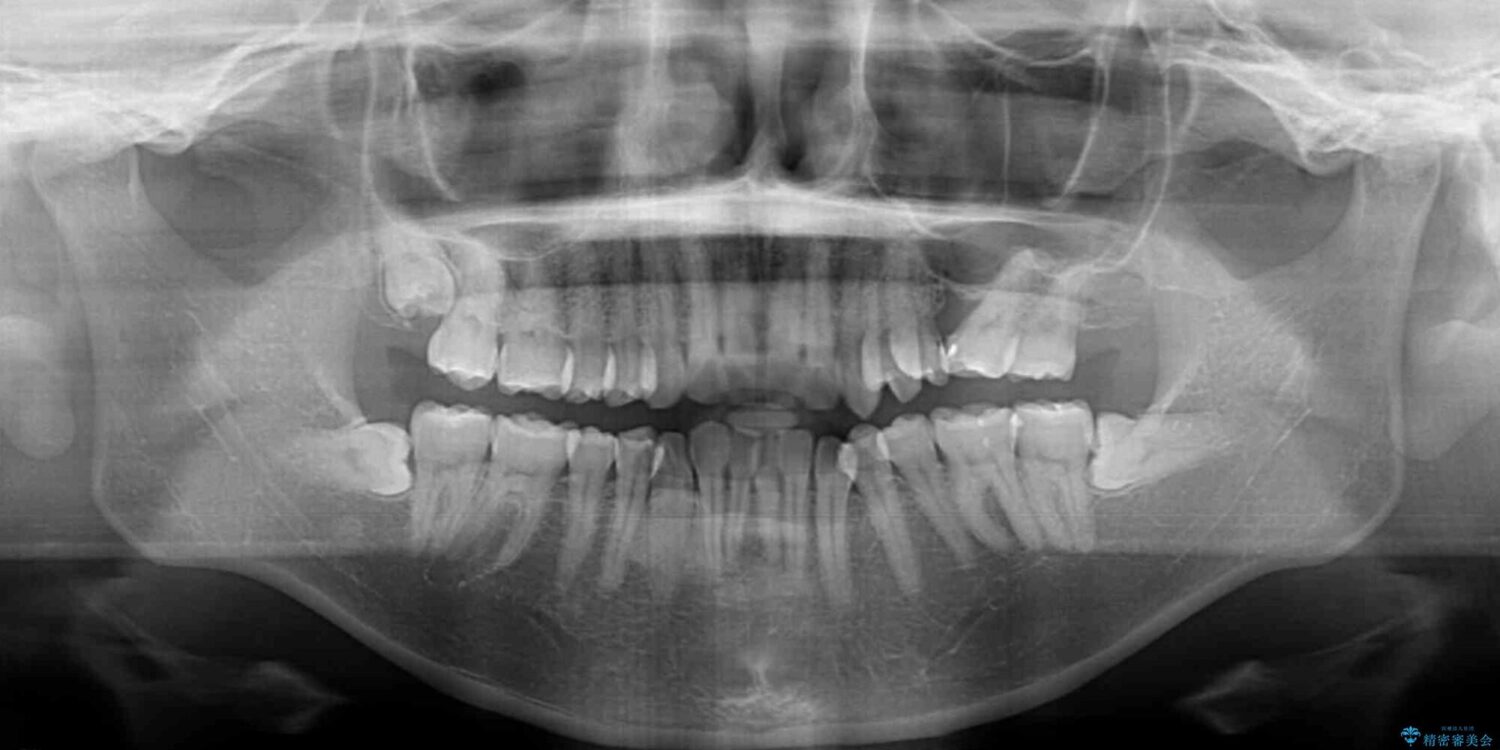

全体的なデコボコと、以前抜歯した歯のスペースを閉じた部分が気になるとのことで来院された患者様です。

左上第一大臼歯を抜歯した際に、スペースを閉じたそうですが、歯が傾斜してものが挟まって不快とのことでした。

インビザライン矯正で全体の歯列と整えるとともに、左上第一大臼歯部にはスペースを作り、インプラントによる補綴治療を行うこととしました。

治療前

• インビザラインによる矯正治療と奥歯のインプラント治療 治療前画像